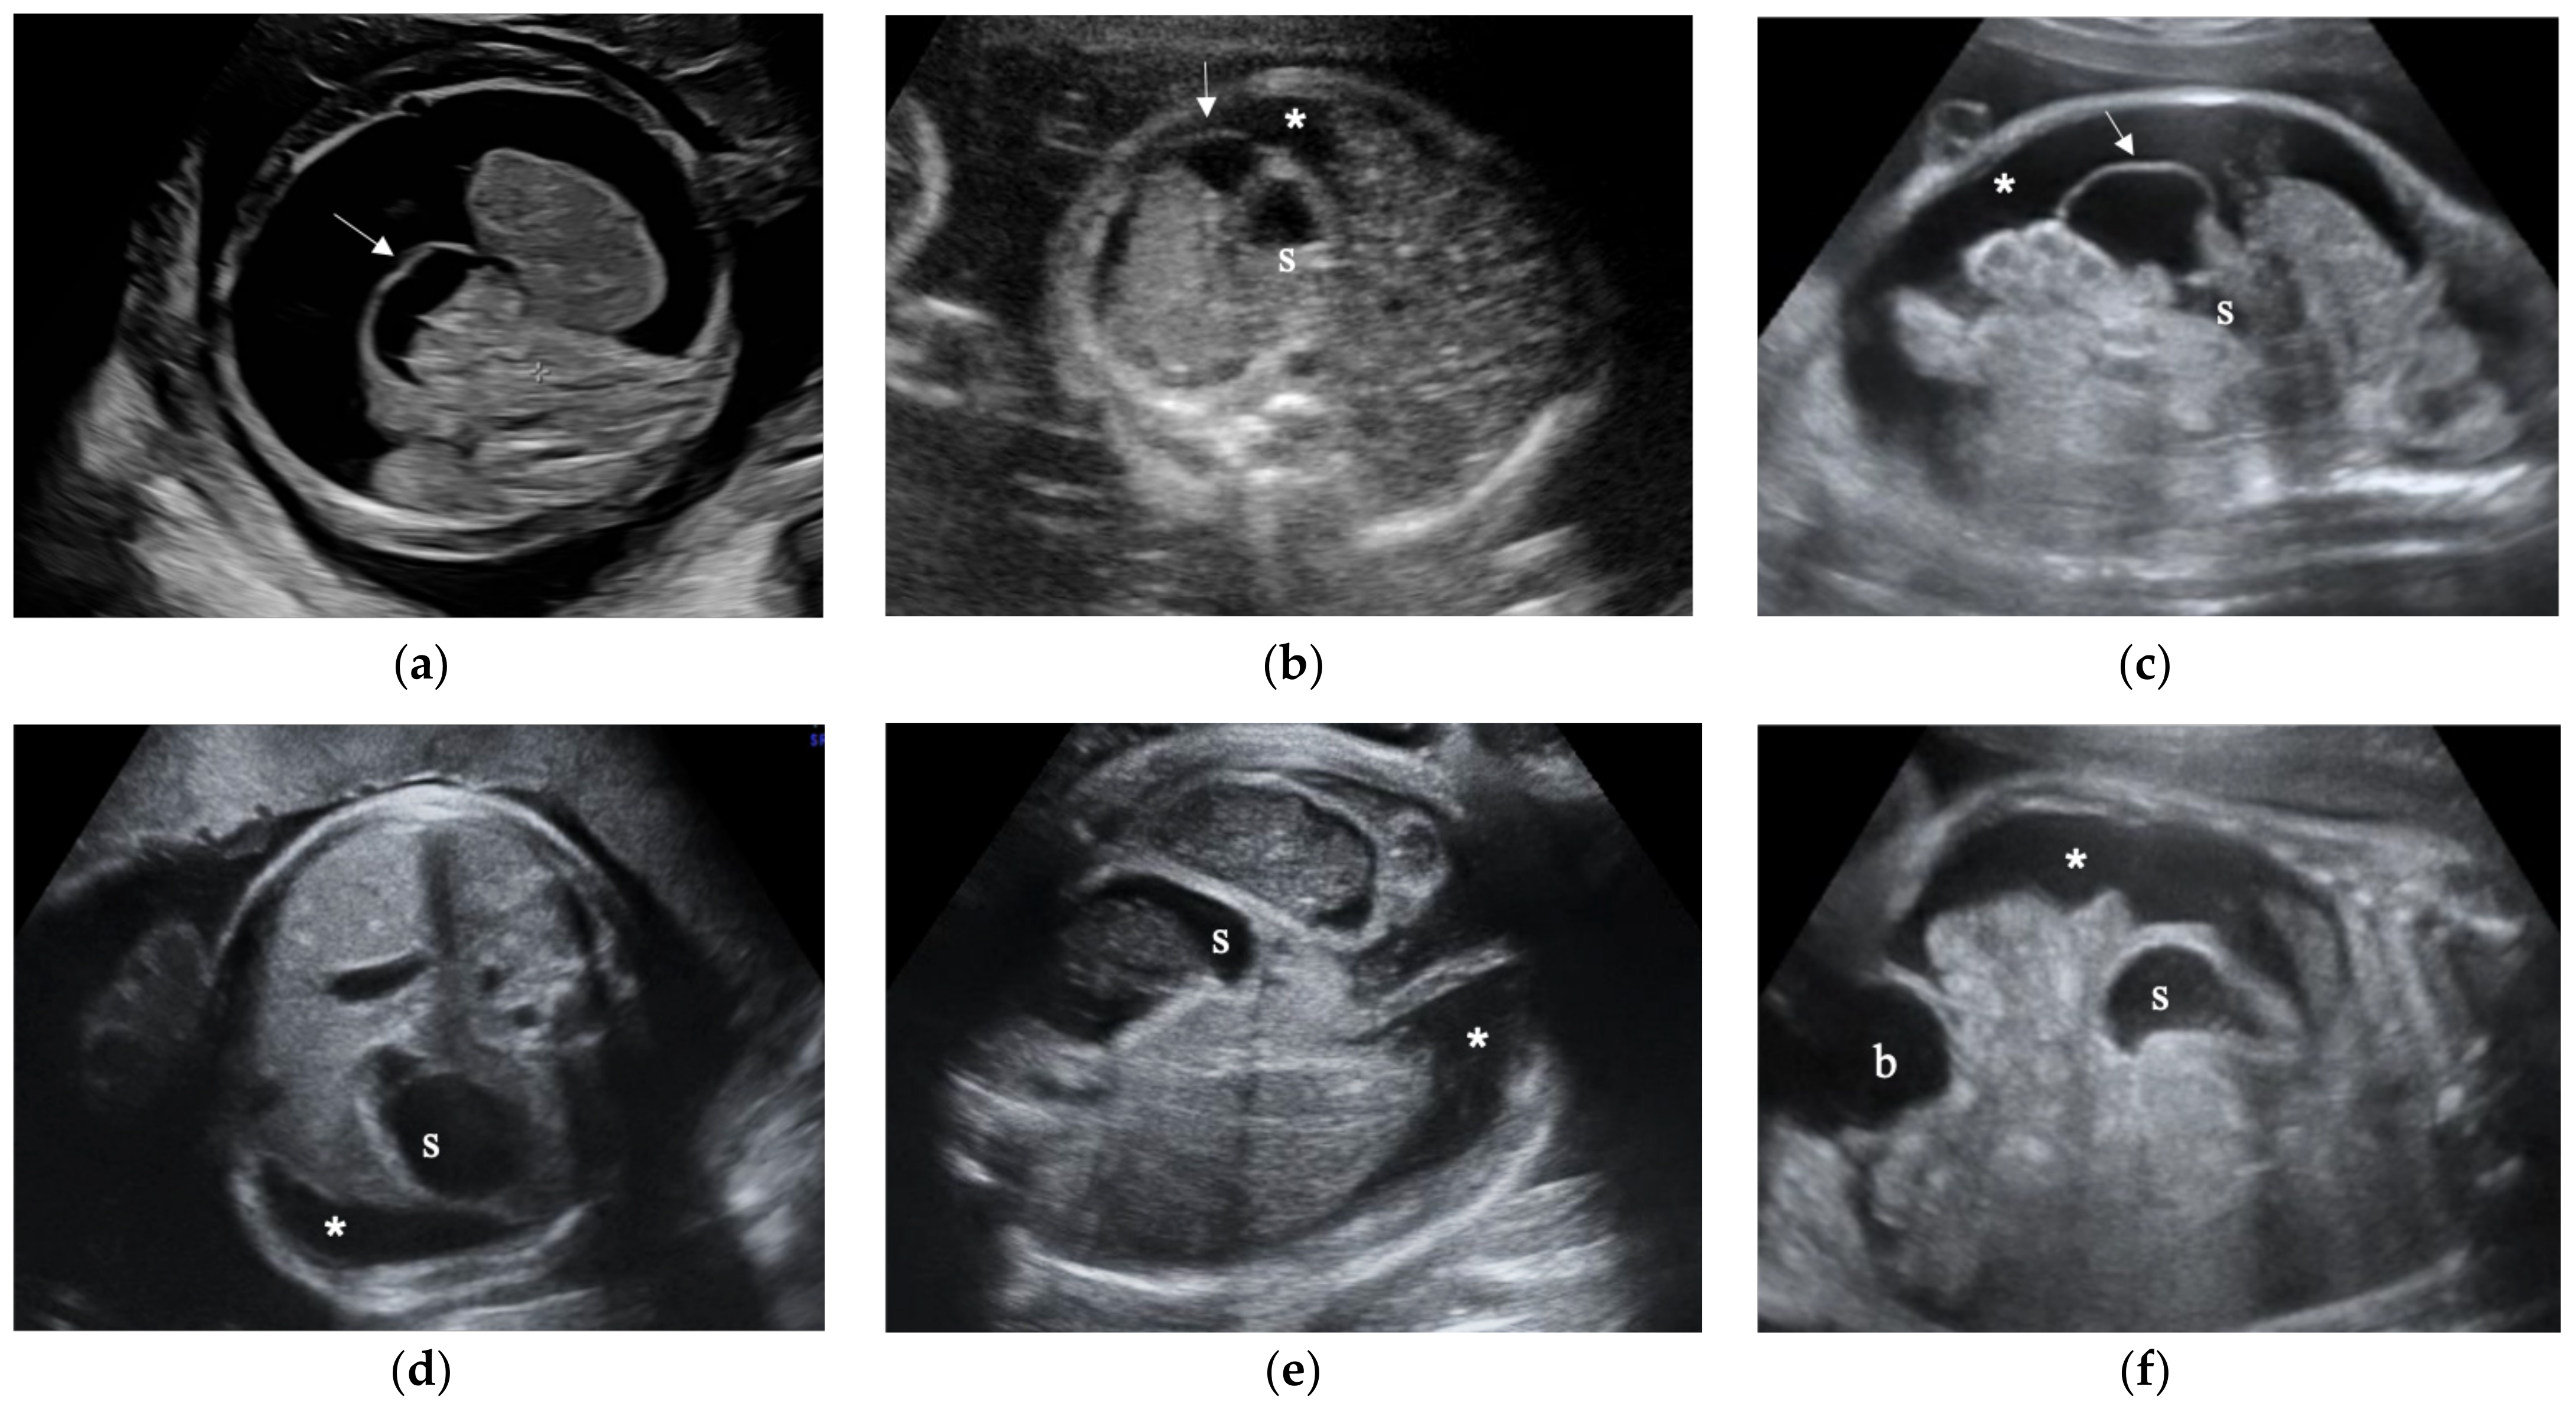

3.2. Fetal Greater Omentum with Ascites

3.3. Fetal Greater Omentum Was Not Observed in Three Cases of Meconium Peritonitis